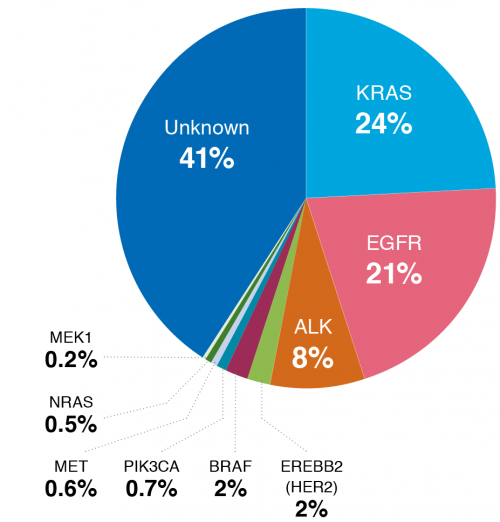

אושרו מספר תרופות אשר פועלות במגוון מנגנונים מולקולריים והן מהוות את הטיפול בחולים המבטאים מוטציות ספציפיות (טיפולים ביולוגיים מכווני מטרה). כ־25 אחוזים מכלל חולי האדנוקרצינומה מבטאים מוטציות שלהן קיים טיפול נקודתי. טיפול מוכוון מטרה משיג שיעורי תגובה גבוהים, שיפור בהישרדות הכוללת, משכי תגובה ארוכים ופרופיל רעילות משופר, אך לרוב מתפתחת עמידות לטיפול זה ונדרשת התאמת טיפול מחודשת[3].

מבין כלל היעדים הנקודתיים, האימפקט הטיפולי הבולט ביותר הוא באלה הנושאים טרנסלוקציה לגן ה-alk. חולים אלה מגיבים בצורה מהירה, ארוכת שנים וניתן להציע להם רצף טיפולי של מספר קווים. במעקבי קבוצת חולים גדולה במיוחד בעלי טרנסלוקציית alk, חלקם אובחנו למעלה מ־3 שנים ומרביתם עדיין בקו הטיפולי השני בלבד וחיים חיים כמעט רגילים. ומשכך, חובתנו כקהילה רפואית, לעשות ככל הניתן להגיע לאבחון מדויק ומהיר ולהנגיש ככל היותר תרופות המתאימות למחלה זו.

כ־5 אחוזים מחולי האדנוקרצינומה הם בעלי טרנסלוקציה בגן alk. חולים אלה הם צעירים (טווח 19 עד 70, גיל חציוני = 52), עם העדר היסטוריה של עישון.